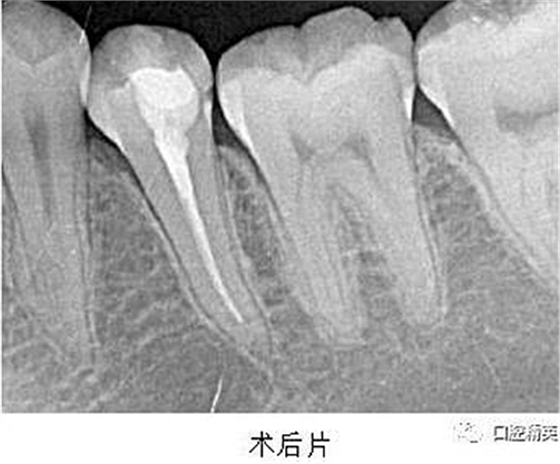

處置:經(jīng)患者及家屬知情同意后,35 局麻,放置橡皮障,去腐,開(kāi)髓,可見(jiàn)黑色感染物流出,定位根管口,建立直線通路,10# K 銼疏通根管,確定工作長(zhǎng)度(19mm),機(jī)用鎳鈦器械(M3),次氯酸鈉全程浸泡沖洗,預(yù)備根管至 35 號(hào),0.04 錐度,2ml EDTA 沖洗液緩慢勻速?zèng)_洗,超聲蕩洗。試主尖 X-ray 可見(jiàn)恰充,吸潮紙尖拭干根管,導(dǎo)AH-Plus 糊劑,連續(xù)波熱牙膠垂直加壓充填,術(shù)后 X-ray可見(jiàn)根管恰充,SDR 封閉根管口,復(fù)合樹(shù)脂充填窩洞,恢復(fù)牙齒形態(tài),調(diào)牙合,拋光。醫(yī)囑

2、扁平根管充填時(shí),應(yīng)該采用混合技術(shù)。因?yàn)橹餮滥z尖往往不適合扁平根管的形態(tài),使得攜熱器很容易將主牙膠尖全部帶出根管?;旌霞夹g(shù)是將連續(xù)波熱牙膠垂直加壓充填法和側(cè)方加壓充填法混合使用,即在插入主尖之后,使用側(cè)方加壓器加壓,追加數(shù)根副尖,直至根尖區(qū)充填致密,繼而使用攜熱器切斷,垂直加壓,熱牙膠回填。

3、根管充填完成之后,要使用流動(dòng)樹(shù)脂或者 SDR 嚴(yán)密封閉根管口,酌情墊底,優(yōu)化洞型,之后再行樹(shù)脂充填或嵌體等的修復(fù)。本例建議行嵌體修復(fù),患者由于個(gè)人時(shí)間問(wèn)題,希望暫緩修復(fù),于是采用樹(shù)脂充填修復(fù)術(shù)。